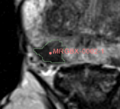

• To establish the methods found in Heterogeneity CAD for prostate MRI purposes

• Establish Slicer pipeline for prostate MRI texture analyis